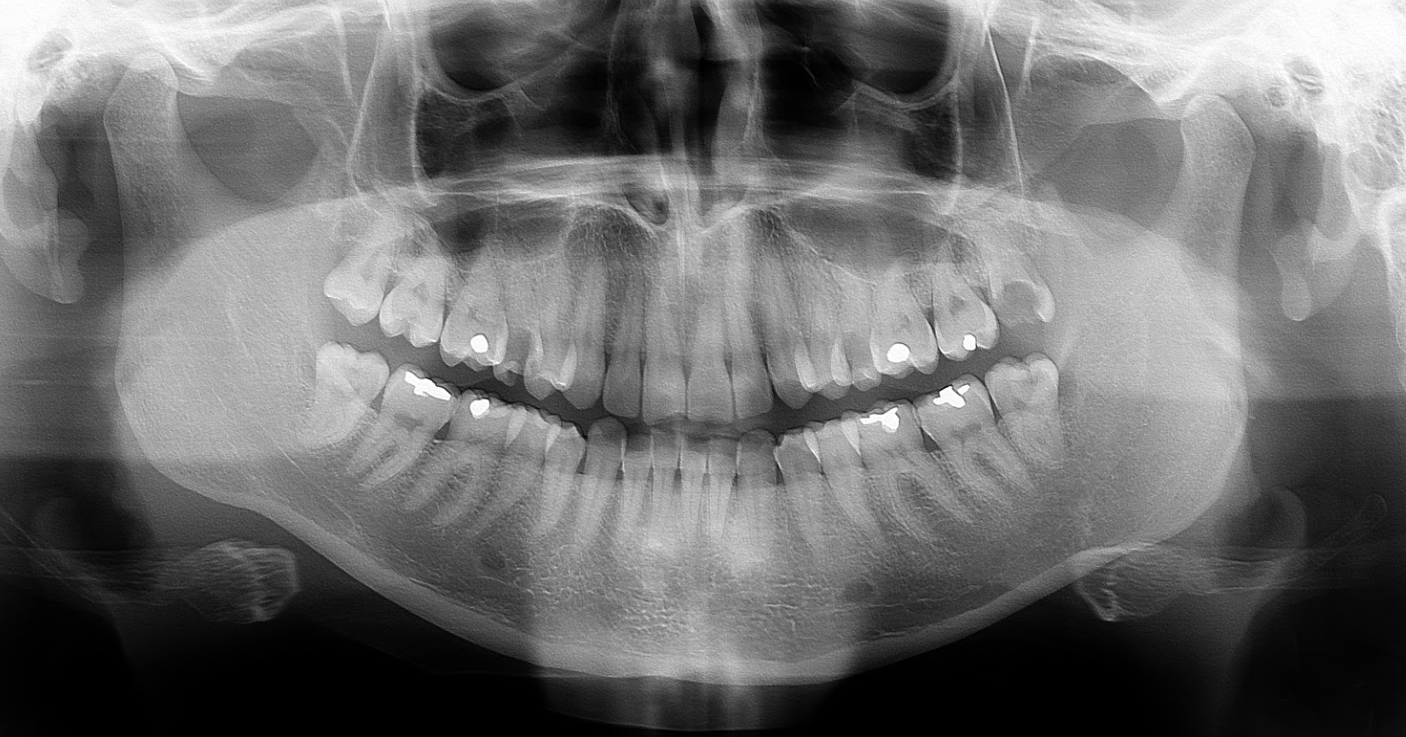

Starostlivosť o zuby by mala byť jednou z najhlavnejších priorít každého človeka. Ignorovanie preventívnych prehliadok či nutných zákrokov sa totiž môže ľahko zvrhnúť v neznesiteľnú bolesť aj dlhodobé následky, ktoré už pár minút u zubára bohužiaľ nevyrieši.

Stomatológia je však náročná a komplikovaná veda, preto je najlepšie zveriť sa do rúk odborníkom. Svoje vedomosti o tvojich zuboch si môžeš overiť v kvíze nižšie.

Schill Dental Clinic búra aj tradičný stereotyp o tom, že u zubára pred zákrokom najprv hodinu sedíš pri časopisoch a čakáš. Do košickej kliniky sa totiž objednáva na čas, nečaká sa na lekárov a netreba nikam cestovať ani po RTG či CT vyšetrenia, keďže sú všetci špecialisti prítomní pod jednou strechou.